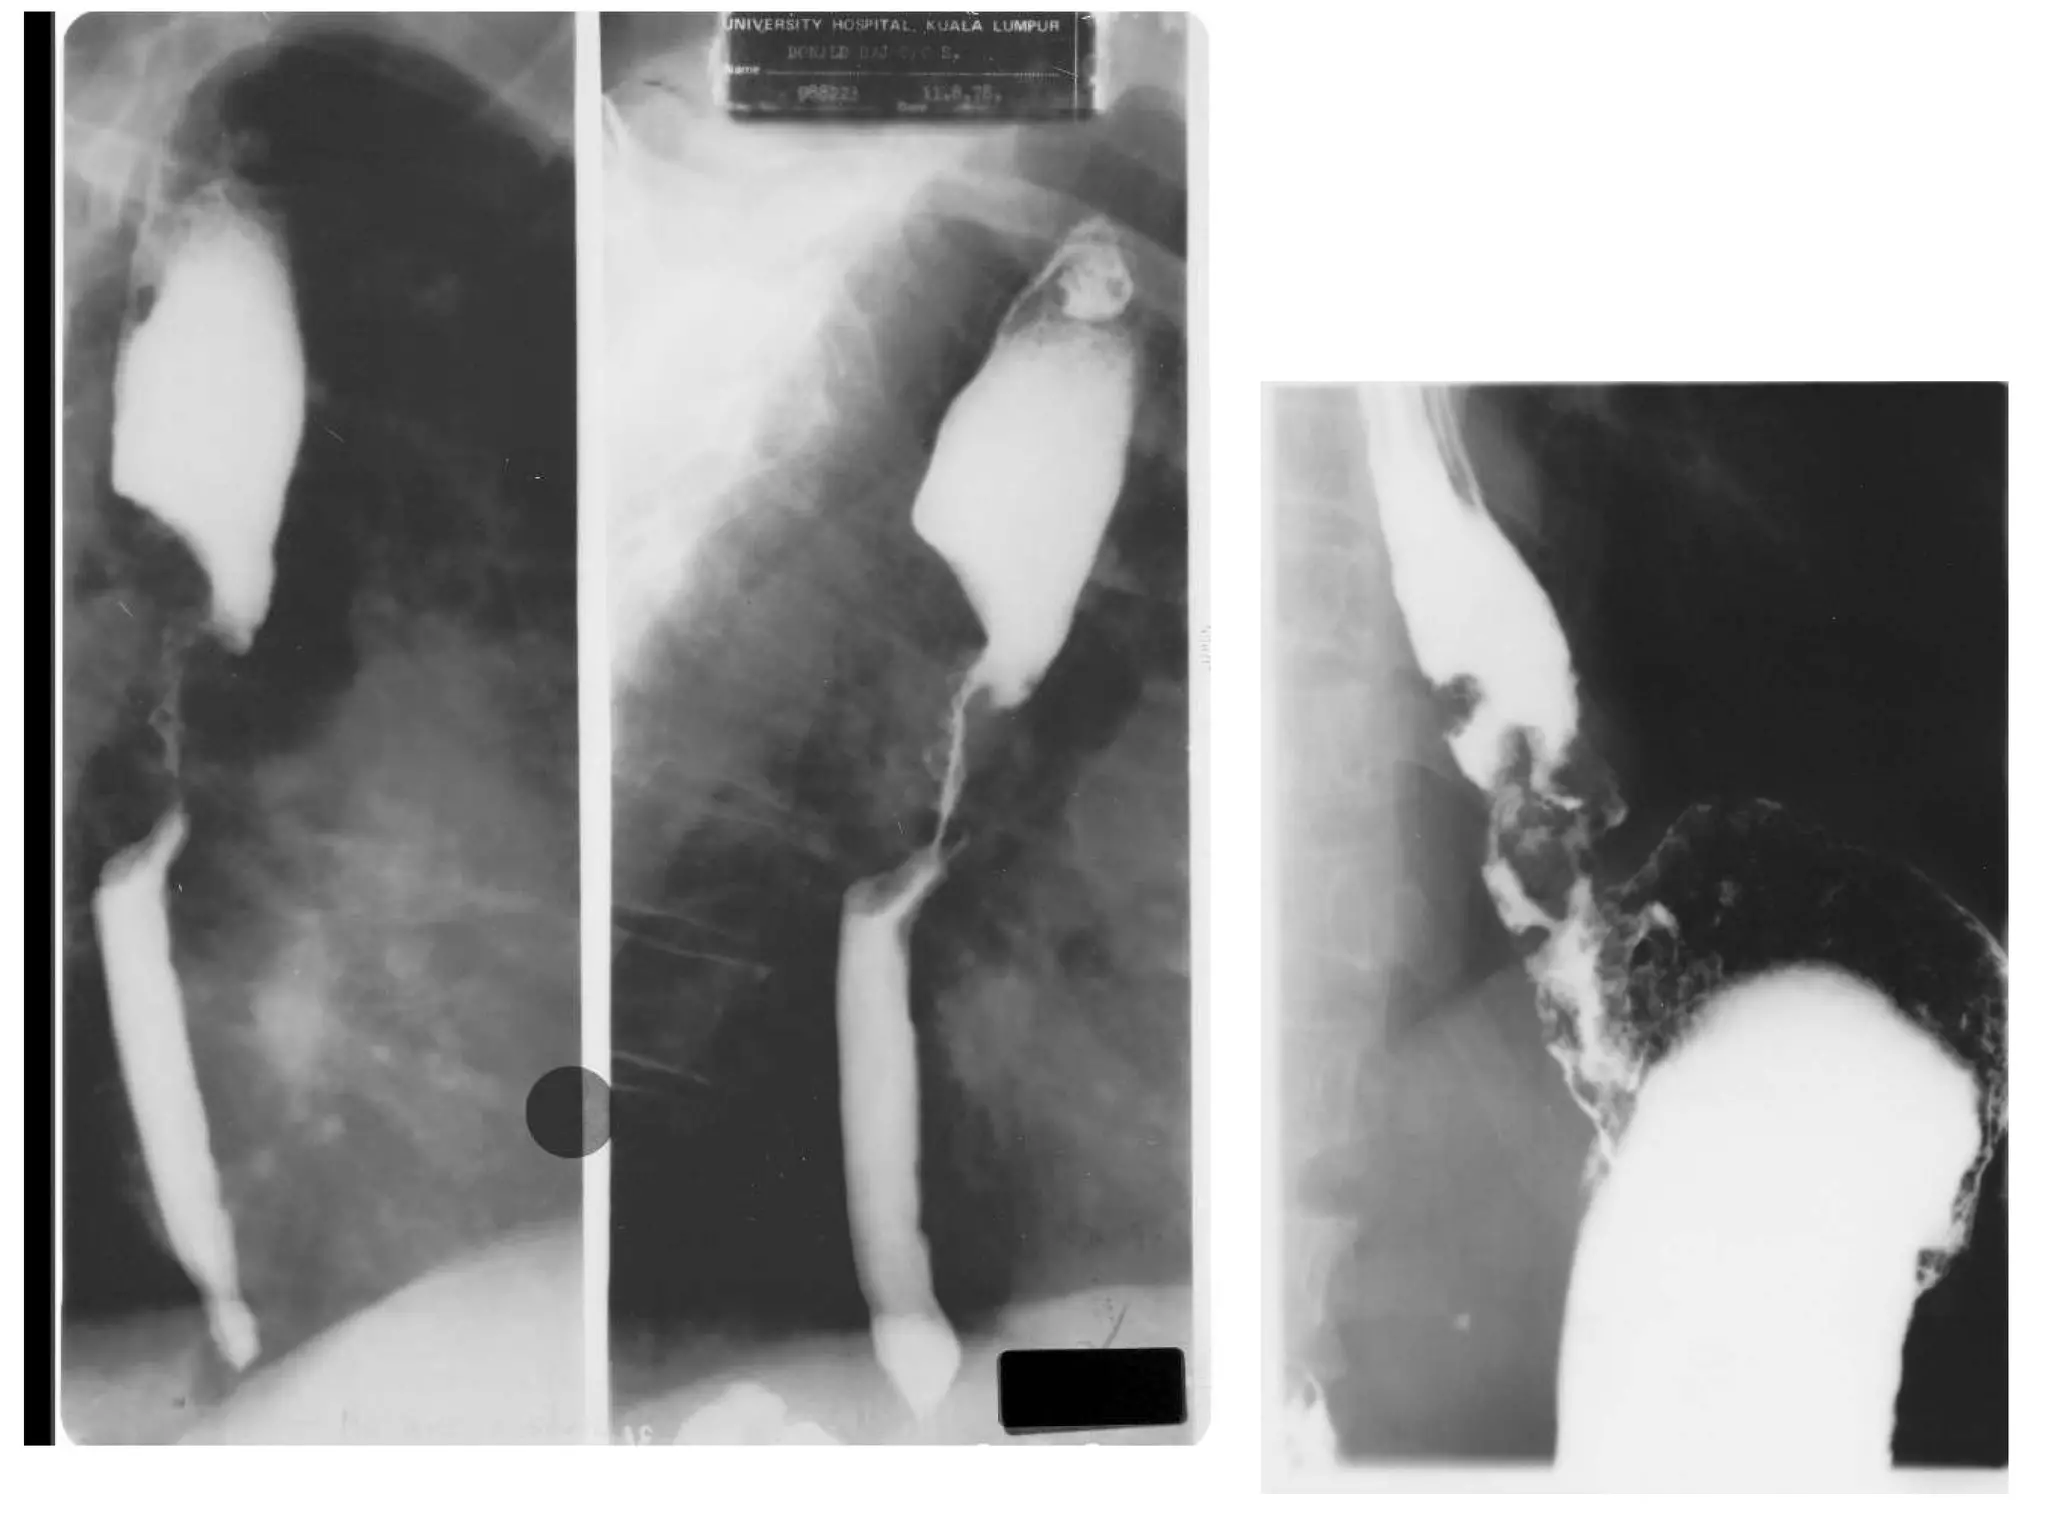

Esophageal CA What is it? Barium swallow Describe? Irregular stricture Shouldering of upper end Dx? Ca esophagus Presenting S&S? Dysphagia LOW LOA

Esophageal CA Whatis it? Barium swallow Describe? Irregular stricture Shouldering of upper end Dx? Ca esophagus Presenting S&S? Dysphagia LOW LOA